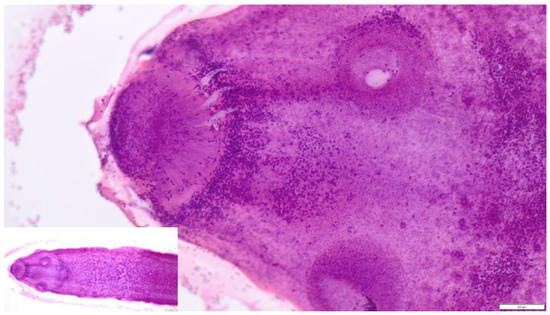

Is Taenia crassiceps Cysticercosis a Threat to Dogs? Description of Macro- and Microscopic Lesions in a Dog. Case Report and a Review of the Literature

by Małgorzata Kandefer-Gola, Kacper Żebrowski, Rafał Ciaputa, Marta Demkowska-Kutrzepa and Stanisław Dzimira

Pathogens 2026, 15(1), 25; https://doi.org/10.3390/pathogens15010025 - 24 Dec 2025

Taenia crassiceps is a cestode capable of causing severe and atypical cysticercosis in accidental intermediate hosts, including domestic dogs. Here we report a fatal disseminated T. crassiceps infection (cystiscercosis) in a 4-year-old castrated male German Shepherd from Poland that had been undergoing long-term [...] Read more.

Taenia crassiceps is a cestode capable of causing severe and atypical cysticercosis in accidental intermediate hosts, including domestic dogs. Here we report a fatal disseminated T. crassiceps infection (cystiscercosis) in a 4-year-old castrated male German Shepherd from Poland that had been undergoing long-term prednisone therapy for Addison’s disease. The dog developed multiple soft subcutaneous nodules containing numerous asexually proliferating cysticerci. Necropsy revealed extensive dissemination of larvae throughout the subcutis and the thoracic and abdominal cavities, accompanied by serosanguineous effusions, necrosis, and chronic inflammatory lesions. Histological examination demonstrated cestode larvae with a scolex bearing two rows of hooks, consistent with T. crassiceps. Immunosuppression and endocrine alterations, including chronic glucocorticoid treatment and low levels of testosterone, likely promoted rapid asexual proliferation of larvae. A literature review shows that although dogs are definitive hosts of T. crassiceps, immunosuppressed individuals may also serve as accidental intermediate hosts. Early cytological evaluation of subcutaneous nodules may facilitate faster diagnosis and treatment decisions. Given the zoonotic potential of T. crassiceps and the increasing number of European cases, this parasitic infection should be considered in the differential diagnosis of subcutaneous nodules in immunosuppressed dogs. The presented case underscores its epidemiological relevance within the One Health framework. Full article